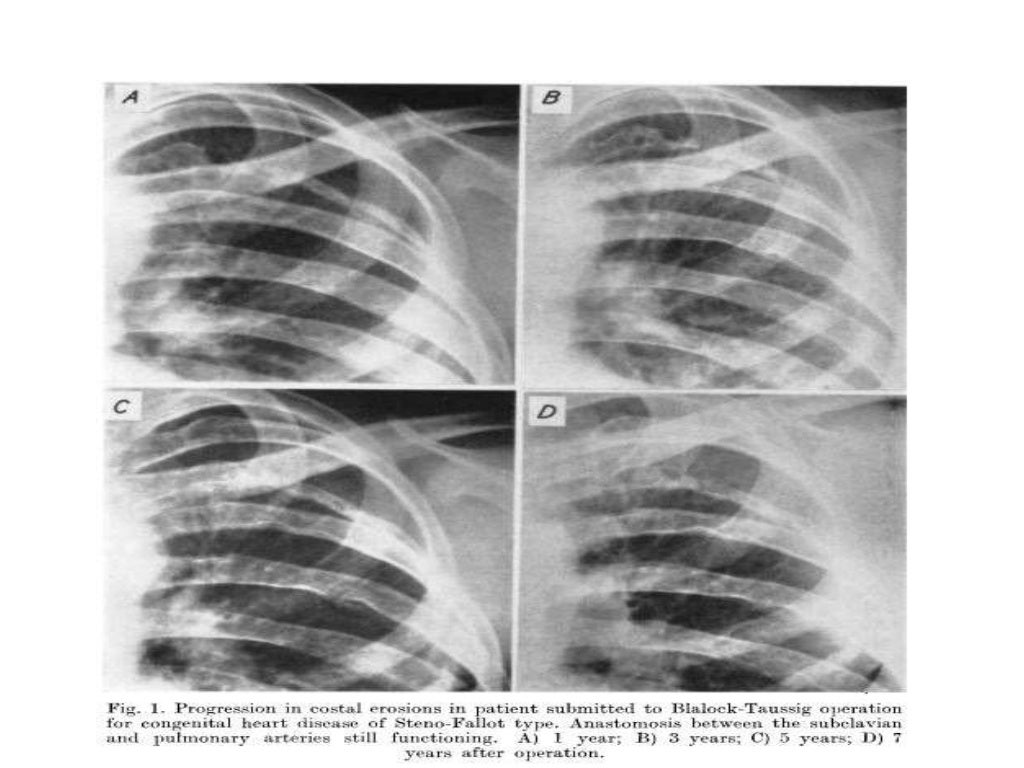

Figure 1 from Rib Notching following the BlalockTaussig Operation Rib Notching Definition This article discusses how ribs are involved in a variety of traumatic, metabolic, inflammatory, neoplastic, and congenital disorders. Acute rib infections are seen as focal areas of bone destruction, whereas chronic infections may manifest as periosteal reaction or a bone sequestrum. Rib notching are deformities that affect the upper surface of the rib, the lower surface of the rib (roesler’s. Rib Notching Definition.